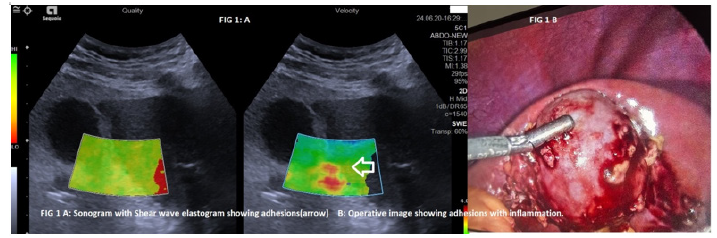

Laparoscopic Cholecystectomy has become the procedure of choice for gall bladder removal worldwide [1]. The surgeon is often mired by the difficulties of procedure which not only lead to increased operative time, prolonged hospital stay and even procedural complications like common bile duct injuries, incomplete removal, biliary collections and hematoma formation [2]. There has been an incessant desire by the laparoscopic surgeon to have a pre- operative classification about the gall bladder so as to have an idea of the pre- operative difficulty what can be called as the good, bad or ugly gall bladder [3-5]. Ultrasound being the most commonly used imaging tool for gall bladder assessment does not tell about the status of gall bladder wall i.e. thickness, edema but also about the luminal contents and initial studies done were based on these parameters categorized the gall bladder into good or bad categories with those showing a wall thickness of more than 4mm as bad [5]. Gall bladders with stone size more than 25mm were also labeled as difficult procedures in some studies [6]. As experience and imaging improved criteria of gall bladder volume, distension and cystic duct length were also added to further elaborate the differentiation between the above groups [7]. Inspite of all the above sonographic parameters the sensitivity and specificity of ultrasound to predict difficult gall bladder surgery has been 75% and 87% respectively [5-7]. The most challenging part has been the detection of pericholecystic adhesions. Studies based on ultrasound alone used presence of pericholecystic stranding, fluid, contracted or non -visualized gall bladder lumen as the criteria all of which were indirect indicators of adhesions and hence had a variable accuracy [6]. Recent studies [8] have shown that use of Shear Wave Elastography (SWE) was more useful and detected pericholecystic adhesions based on increased stiffness of gall bladder wall and surrounding parenchyma. SWE also quantified the level of stiffness and fibrosis in pericholecystic locations which enabled the detection of difficult cholecystectomies i.e. ugly gall bladder and differentiated it pre-operatively from the good and bad gall bladders. Good gall bladders had normal volume of at least 40 cc and a distended lumen with wall thickness of less than 2.5mm and absent adhesions while bad gall bladders had normal distension with wall thickness more than 2.5mm and with moderate adhesions while ugly gall bladders had loss of volume with severe peri- cholecystic adhesions. Coupled with ugly gall bladders were also those patients with congenital morphological anomalies including short cystic duct, ectopic gall bladder location which added to surgical difficulty.

To summarize with the use of modern imaging tools and enhanced sonographic skills one is able to pre-operatively map the level of difficulty of a laparoscopic surgery and categorize the gall bladder as good, bad or ugly and thus help surgeon in better operative planning (Figure 1).